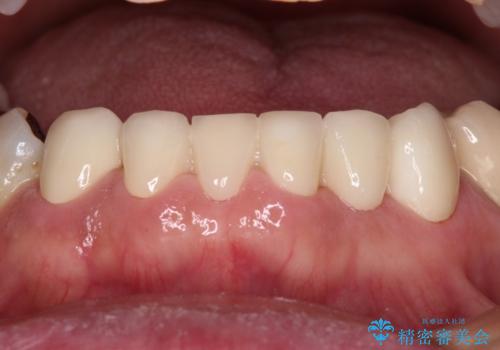

上顎の矮小歯は隙間が多く、歯軸の傾斜も大きかったため、部分矯正により補綴治療前に歯の位置を整えることとしました。

下顎の乳歯は支台歯として機能することは困難と思われたので、事前に抜歯をし、上顎の矯正治療終了のタイミングに合わせて、セラミックブリッジにて補綴治療することとしました。

前歯部はディープバイトという、上顎前歯が下顎前歯に深く覆い被さる咬合であったので、理想的には全顎矯正が必要となりますが、今回は患者希望により前歯部のみの部分矯正で対応しました。そのため下顎犬歯の神経を取り除くことになってしまったのは心残りであります。